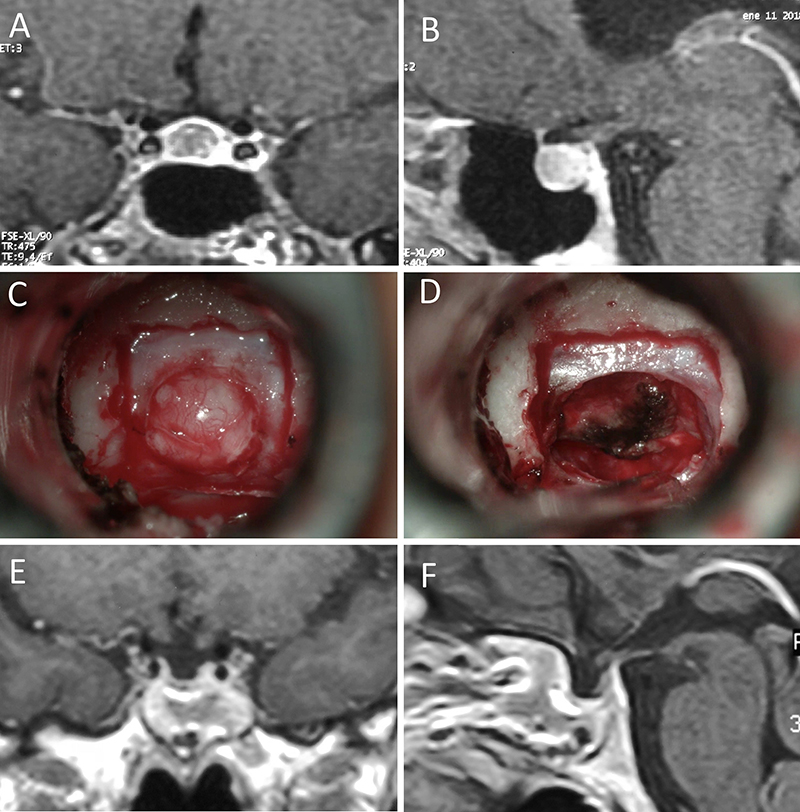

Figura 5: Apoplejía hipofisaria hemorrágica en un hombre de 32 años. El paciente presentó cefalea y parálisis completa del III par. Tuvo restitutio ad integrum en el seguimiento. A-B: RM preoperatoria; C-D: intraoperatorio; E-F: RM postoperatoria.

Figura 6: Apoplejía hipofisaria hemorrágica en un hombre de 55 años. El paciente presentó cefalea, déficit visual y parálisis completa del III par. Evolucionó favorablemente tras la cirugía, revirtiendo el cuadro. A-B: RM preoperatoria; C-D: intraoperatorio; E-F: RM postoperatoria.